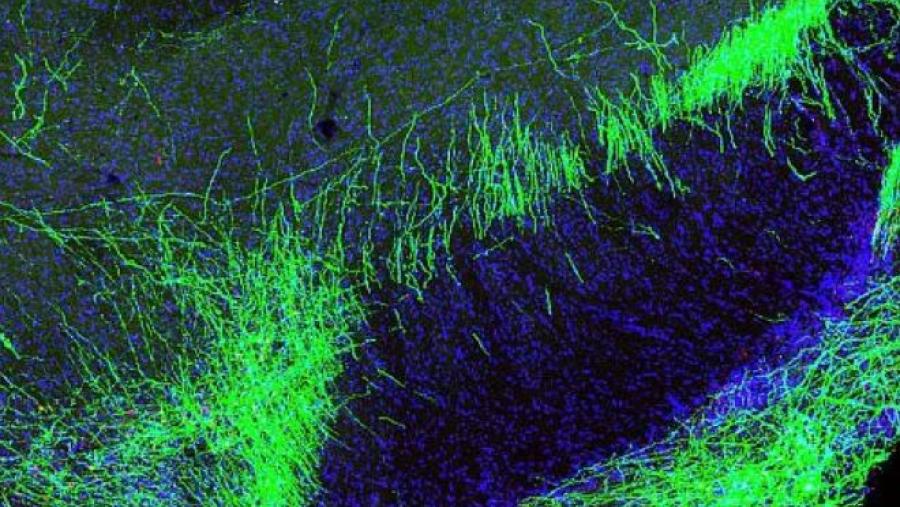

Image

Scientists identified a group of neurons in mice that blunt pain within the brain. Such neurons could be promising targets for new non-addictive therapies for chronic pain.

Published: June 4, 2020

Topics:

Novel Targets